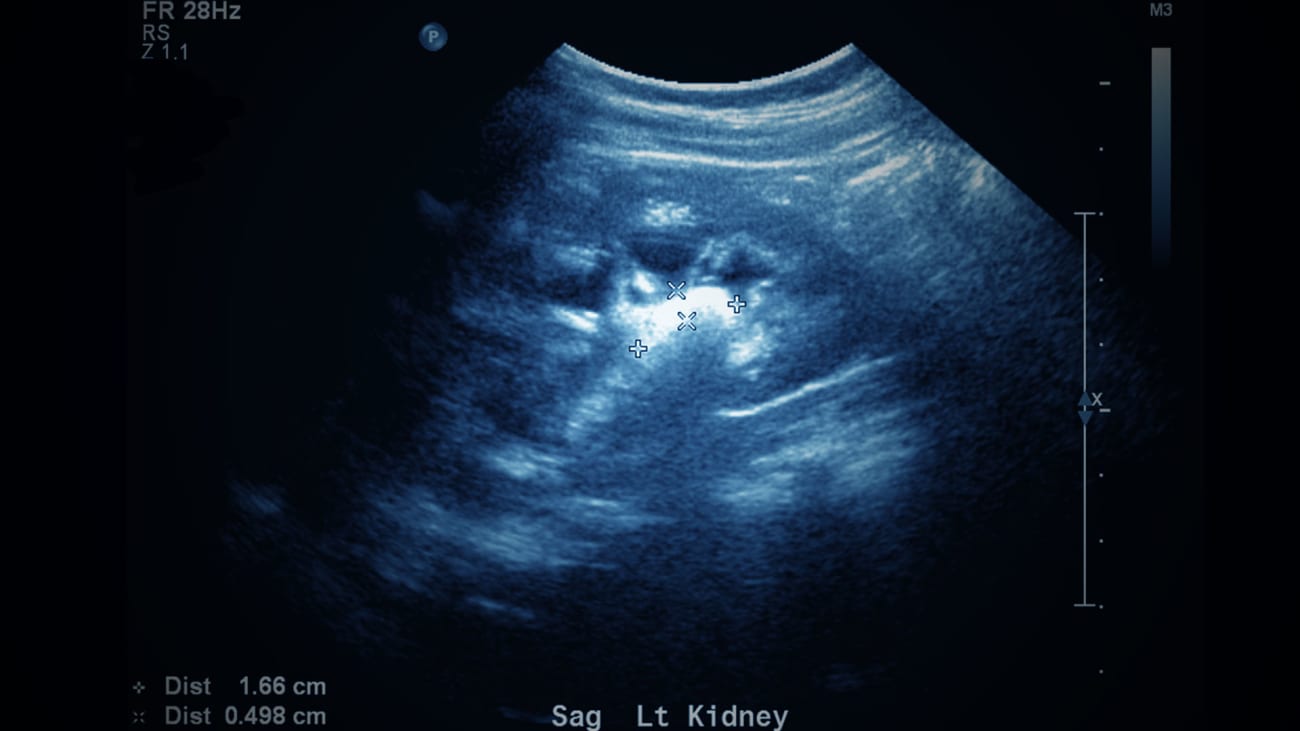

Mount Sinai Pediatric Stone Clinic Diagnoses, Treats, and Prevents Kidney Stones in Children

The Mount Sinai Pediatric Stone Clinic is a comprehensive, interdisciplinary program focused on the diagnosis, management, and prevention of kidney stones in children. Our integrated team of pediatric nephrologists, pediatric urologists, nurse practitioners, technicians, and nutritionists work together to provide personalized treatment. Our goal is to help children with kidney stones live their healthiest possible lives.